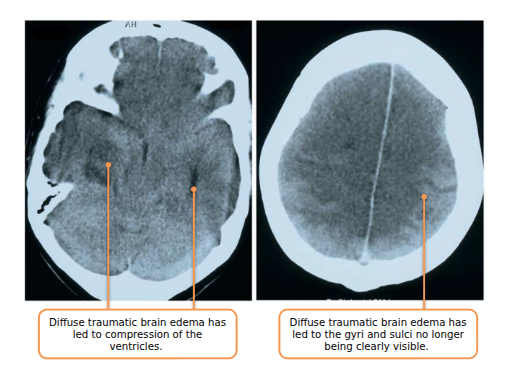

Swelling (aka. Edema) can also occur Can either be cytotoxic edema or vasogenic edema (swelling caused by breakdown of the blood-brain barrier)

It can occur throughout the brain, which is called diffuse traumatic brain edema.